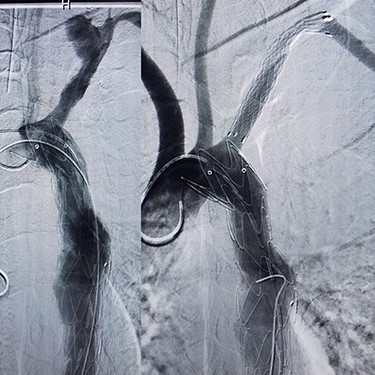

Case 2 — A 32-year-old man with known BD for years, presented to the emergency department with chest pain. We identified left subclavian and thoracic aorta saccular aneurysms on CTA (Fig. 2). Endoxan (1 gr) and Methyl prednisolon pulse (1 gr daily up to 3 days) were injected. The patient underwent a subclavian stent-graft (Fig. 3A) and elective TEVAR (Fig. 3B). Immediate follow-up angiogram revealed the luminal aperture was obtained and it was observed that the pseudoaneurysm remained occluded without a sign of leakage or endoleak. Tablet of prednisolon (5 mg) was prescribed twice daily.

(A) Angiography after stent-graft placement of left subclavian (right), (B) thoracic aorta (left).